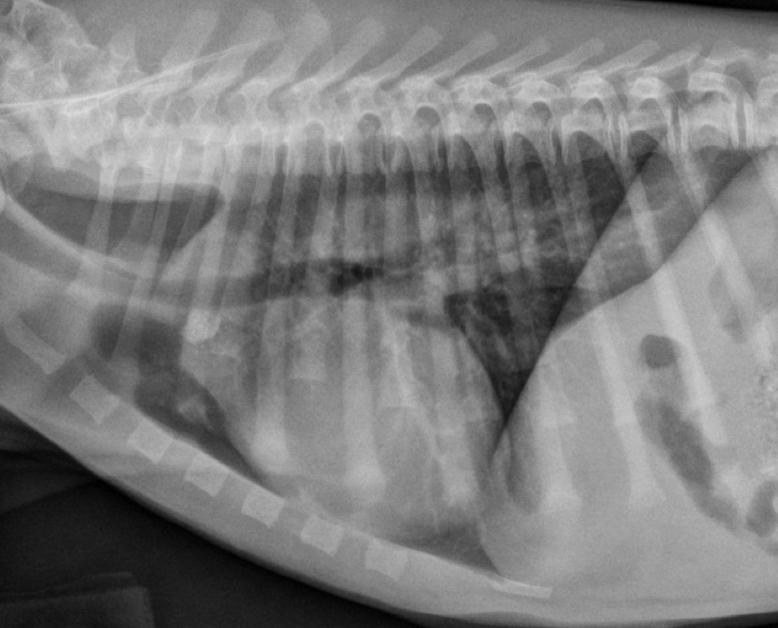

A

Juvenile idiopathic megaesophagus